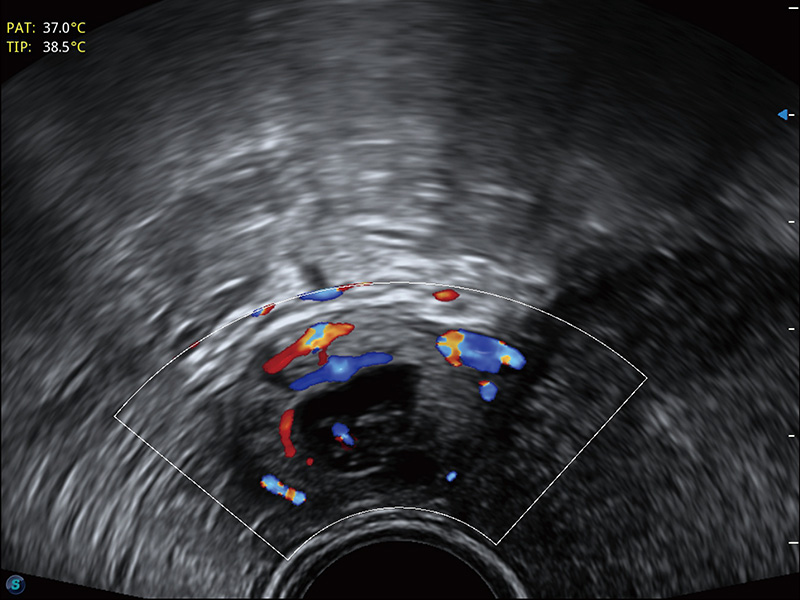

宫外孕血流

输卵管间质部妊娠